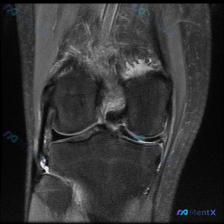

刚整理完一份很有参考价值的膝关节MRI读片病例,核心问题是提问「软骨异常」有什么发现,分享一下完整分析思路。 病例基本影像信息 提供的是膝关节MRI冠状位T2加权图像,仅单张影像,无其他临床病史信息。 影像学核心发现 1. 骨与软骨:股骨远端、胫骨近端骨质可见,股骨内侧髁关节面下可见片状低信号影,伴...